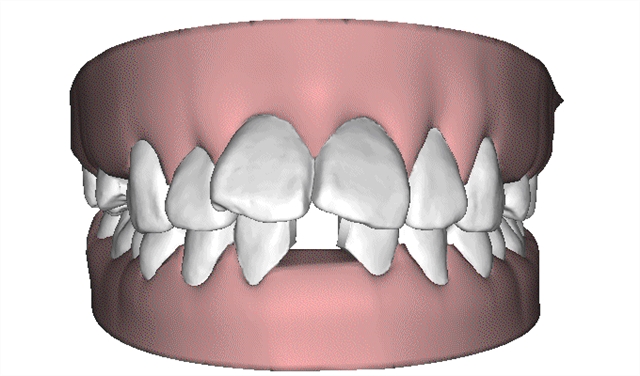

该技术可根据求美者的颌面形态开展个性化设计,通过计算机三维图像技术模拟牙齿移动后生产的每一副矫治器,在戴入后牙齿就会有受力感觉,并向矫治器设计的位置移动,通常每两周更换一副矫治器,牙齿就会从初始的畸形状态逐渐移动至正常排列状态,矫治时间长短取决于患者牙颌畸形的严重程度,一般需要半年到一年时间就能解决牙齿不齐等问题,该技术成为国内外爱美人士矫正牙齿的不二选择。

2应用时代天使无托槽隐形矫治器进行矫治。

治疗方案动画